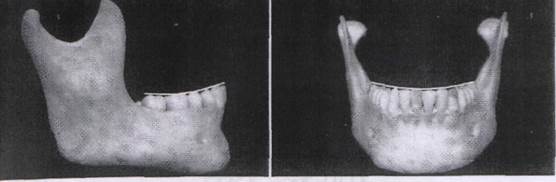

При осмотре дуг сбоку становятся видны мезиально-дистальные аксиальные отношения. Если продлить длинные оси корней в сторону окклюзионных поверхностей через коронки (рис.3.5), то станет виден наклон зубов к альвеолярной кости. На нижнечелюстной дуге как передние, так и задние зубы наклонены мезиально. Второй и третий моляры сильнее наклонены, чем премоляры.

Рис. 3.5. Ангуляция нижнечелюстных зубов. Как передние, так и задние зубы наклонены мезиально.

На верхней челюсти существует другой вид наклонения (рис.3.6). Передние зубы обычно чаклонены мезиально, а самые задние моляры наклонены дистально. Если из бокового вида провести воображаемую линию через кончики щечных бугров задних зубов (моляры и премоляры), то получится изогнутая линия, следующая плоскости окклюзии (рис.3.4), которая выпуклая для верхней дуги и вогнутая для нижней. Эти вогнутая и выпуклая линии в совершенстве подходят друг другу/ когда зубные дуги находятся в окклюзии. Эта кривизна зубных дуг была впервые описана фон Шпеем, и, следовательно, называется кривой Шпея.

Рис. 3.6. Ангуляция верхнечелюстных зубов. Передние зубы наклонены мезиально, а большинство задних зубов наклонены более дистально.

Если посмотреть на дугу во фронтальной плоскости, также можно видеть щечно-язычные аксиальные отношения. В целом, задние зубы верхней дуги имеют небольшой наклон в щечную сторону (рис. 3.7). На нижней дуге задние зубы имеют легкое наклон в язычную сторону (рис. 3.8). Если провести линию через вершины язычных и щечных бугров как правых, так и левых задних зубов, то можно видеть изогнутую плоскость окклюзии (рис.3.4). Кривизна является выпуклой на верхней дуге и вогнутой на нижней. Опять же, если дуги находятся в окклюзии, обе кривые в совершенстве подходят друг другу. Кривая в окклюзионной плоскости, наблюдаемая из фронтального вида, называется кривой Уилсона.

Рис. 3.7. Ангуляция верхнечелюстных зубов. Все задние зубы слегка наклонены в щечную сторону.

Рис. 3.8. Ангуляция нижнечелюстных зубов. Все задние зубы слегка наклонены в язычную сторону.